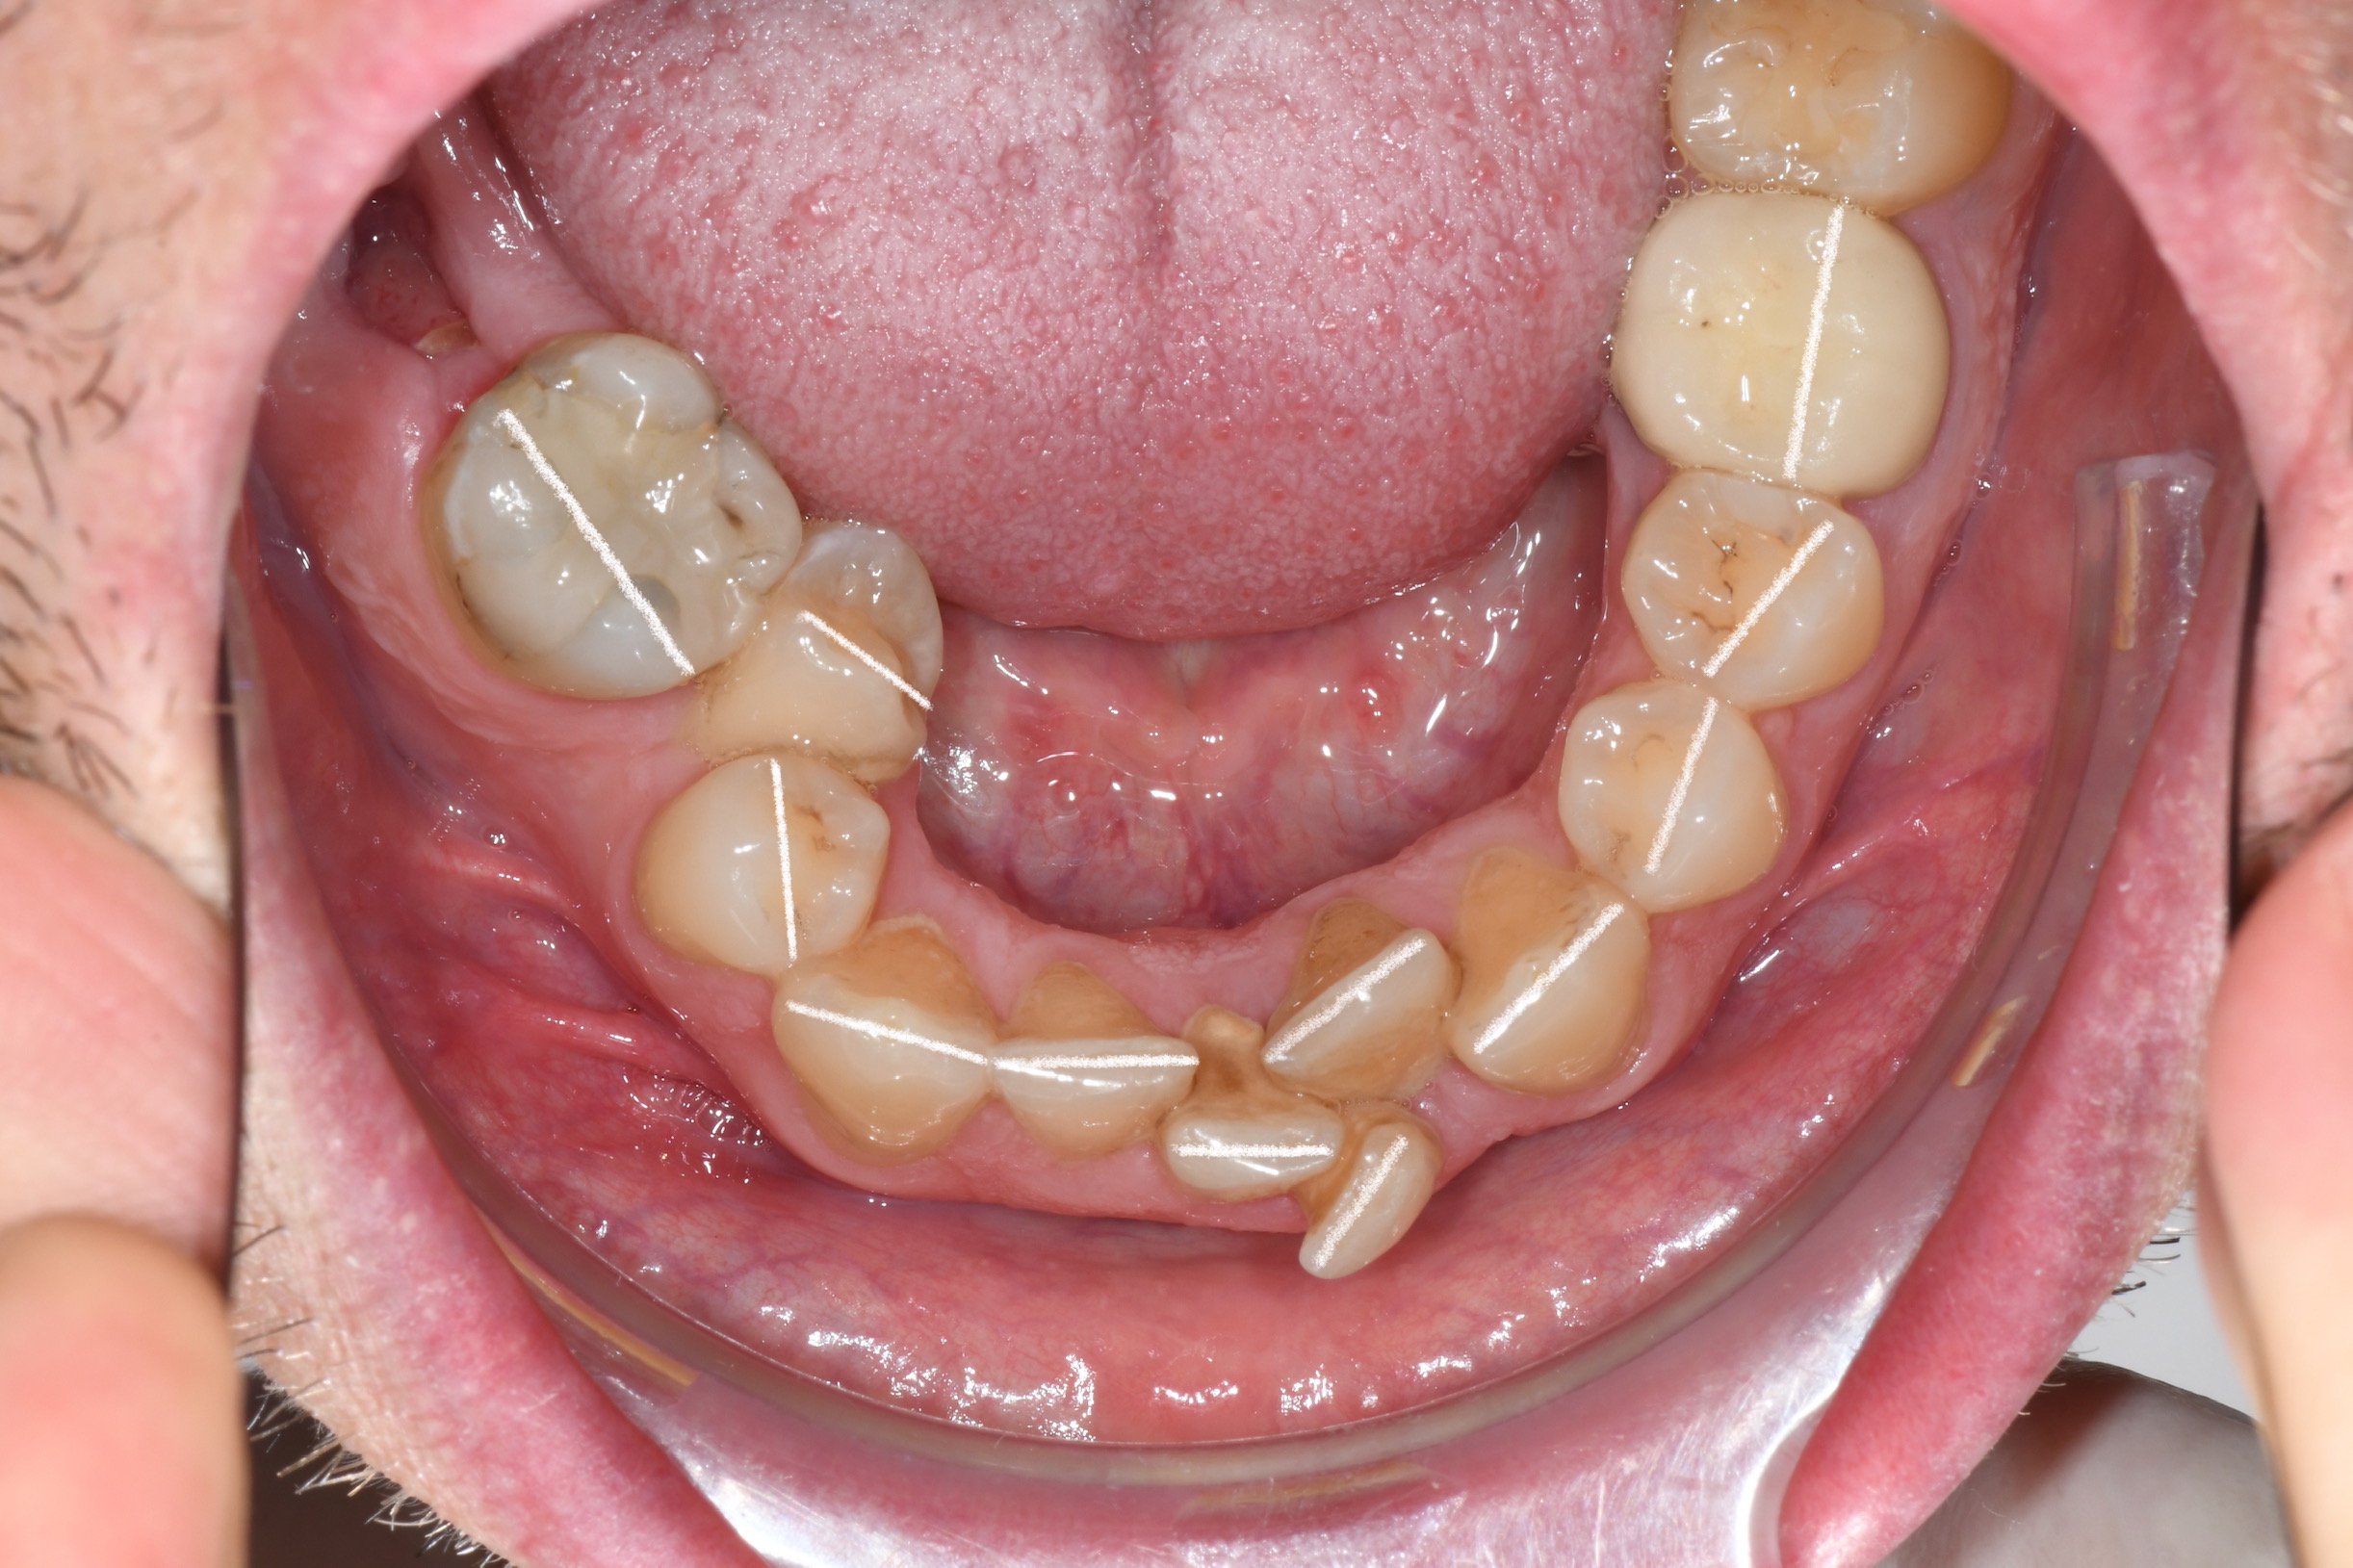

Az elmúlt évekből rengeteg szakmai referenciát tudnánk bemutatni, amelyek különböző fogszabályozási problémákat oldottak meg. Válogatva a több száz esetből, ezen az oldalon olyan képeket, információkat igyekeztünk bemutatni, amelyeknek a segítségével a jövőbeni pácienseinknek azt tudjuk üzenni: A Te fogsorod is lehet gyönyörű!

(Képeket a Pácienseink külön írásos beleegyezésével mutatjuk be!)